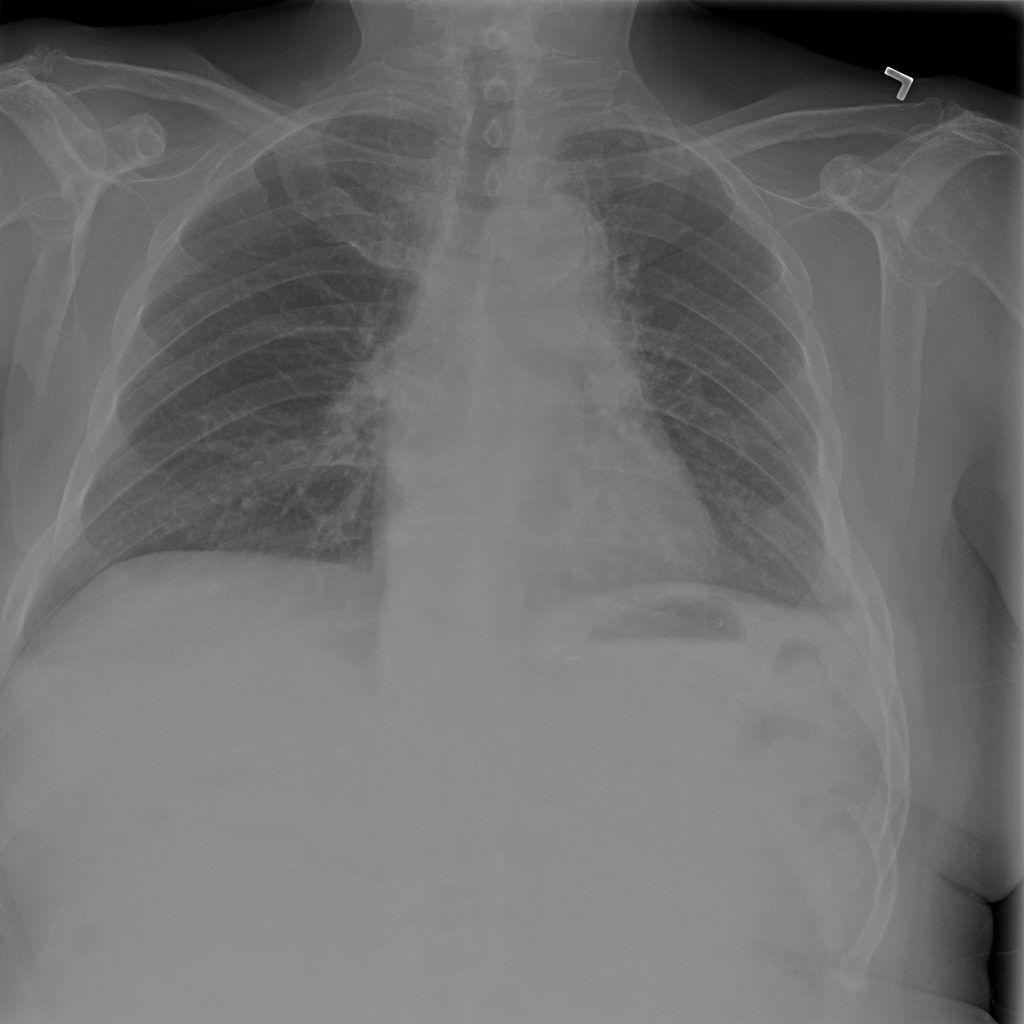

PAT-E066 · IMG-010Fibrosis

PAT-E066 · IMG-010

PA